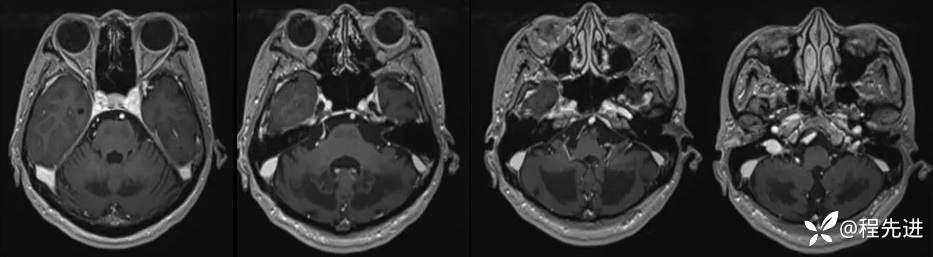

T1:

T2、FLAIR:

DWI、ADC:

颅脑MRI增强: